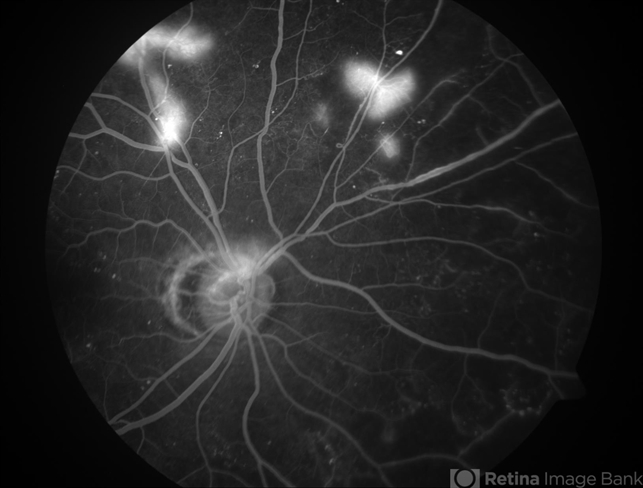

- PDR NVE

- neovascularization (NV)

- Fluorescein angiogram showing leakage secondary to neovascularization in the superior arcades.